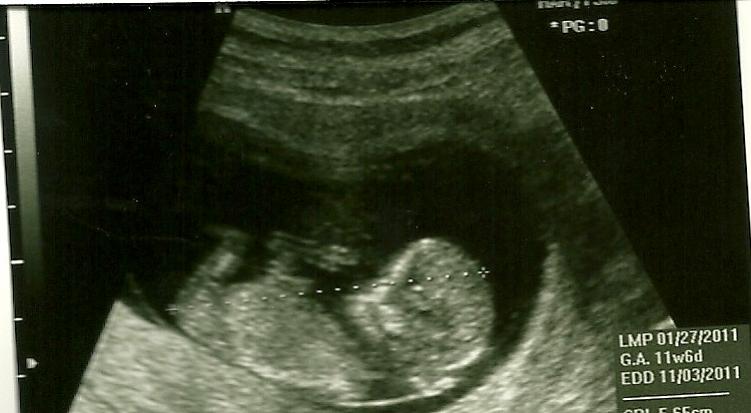

Do you see a nub? 12w2d

I went in for an u's today and babe is measuring 12w2d. I was intently focused on the nub area but didn't see a thing! I have three pics, but I still don't see a nub in any of them. Attachment 154Attachment 155Attachment 156Does anyone see anything that would lead them one direction or another? TIA!

The last one looks like it could be but I can't tell if it is the cursor!

the last pic looks like she is measing from head to actual nub.......im gonna go with girl if thats the nub, GL :)

Is the last pic a nub? Looks like it to me?